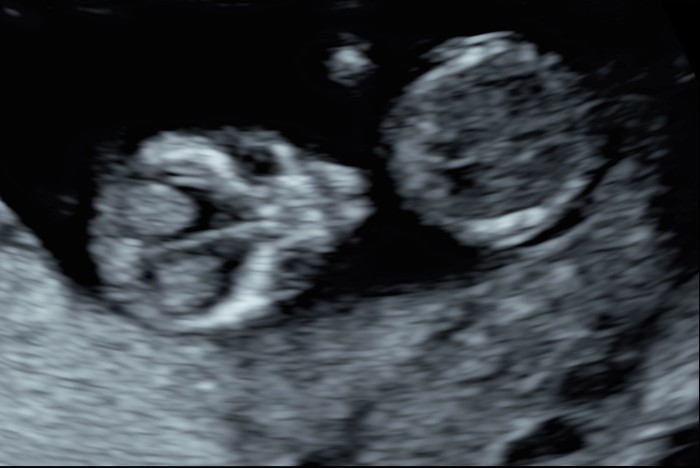

Indipendentemente dalla nostra scelta, è di capitale importanza fare comunque una ecografia fra la 11° e la 13° settimana. Infatti già a questa epoca gestazionale siamo in grado di condurre un’iniziale valutazione morfologica. Ma soprattutto questo è la finestra di opportunità per studiare la translucenza nucale. In realtà questa ampia finestra di tre settimane ha il suo momento più favorevole a 11 settimane e mezza e inizio dodicesima.

Si va a misurare quindi attraverso una ecografia lo spazio dietro la nuca: è una fisiologica raccolta di linfa che tende ad aumentare in diverse situazioni patologiche risultando essere un indice generale di buon andamento della gravidanza dove più è sottile più siamo tranquilli a riguardo di patologie cromosomiche, malformazioni cardiache, ed alcune malattie genetiche.

Questa valutazione può essere integrata da quella del dotto venoso (un piccolo vaso a livello del fegato che ci descrive la funzionalità cardiaca), la presenza dell’osso nasale (in medicina fetale avere un naso di una certa importanza è una cosa rassicurante) e l’assenza del rigurgito della valvola cardiaca tricuspide.

In questi 4/5 centimetri la risoluzione degli apparecchi moderni riesce a fare una prima valutazione morfologica, per vedere che ci siano tutti i “necessori” ed eventualmente anche accessori: cercando è possibile evidenziare il tubercolo genitale (sempre che il piccolo decida di essere collaborante e mostrare le proprie grazie). Si chiama così perché clitoride e pisellino hanno le stesse dimensioni a questa epoca, ma è possibile riconoscerli in base all’angolo rispetto al corpo: parallelo al corpo per le signorine, verso l’alto per i maschietti. Attenzione però la sensibilità, ovvero quanto ci azzecchiamo, è intorno al 60%.

La parte morfologica è molto importante, riusciamo a studiare l’estremo cefalico – a questa epoca il cervello fetale è molto semplice – , il massiccio facciale con occhi, naso bocca, le orecchie sono abbastanza facili da essere evidenziate. Nel torace oltre ai campi polmonari possiamo vedere il cuore battere ritmicamente e confermare la presenza delle quattro camere cardiache. Nell’addome riusciamo ad evidenziare lo stomaco e l’inserzione del cordone ombelicale. Si nota la presenza della vescica e del tubercolo genitale. Si possono esplorare tutti e quattro gli arti.